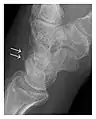

Occult osseous injuries may result from a direct blow to the bone by compressive forces of adjacent bones against one another or by traction forces during an avulsion injury. Lesions in the tibial plateau, hip, ankle, and wrist are often missed. In a tibial plateau fracture, any disruption of the posterior and anterior cortical rims of the plateau should be sought. Impaction of subchondral bone will appear as an increased sclerosis of the subchondral bone (Figure 1). In the hip, posterior acetabular fractures also present subtle radiographic findings. The acetabular lines should then be carefully examined keeping in mind that the posterior rim, which is harder to see on X-rays, is more frequently fractured than the anterior rim (Figure 2). In the wrist, detection of carpal bone fractures is often challenging, with up to 18% of scaphoid fractures radiographically occult. Carpal fractures, especially the scaphoid, are associated with the risk of avascular necrosis. In apparently normal wrist radiographs from symptomatic patients, if there is history of a fall on an outstretched hand with pain in the anatomic snuffbox, suggesting scaphoid injury, the initial examination with posteroanterior, lateral, and pronation oblique views must be complemented by other specific views such as supination oblique and the "scaphoid" view A careful examination of cortices for evidence of discontinuity or offset and cancellous bone for lucency is necessary (Figure 3).[1]

Figure 3: A 26-year-old man presenting with wrist pain after being assaulted. (a) Initial anteroposterior radiograph shows a subtle linear lucency within the scaphoid extending to the scaphocapitate articular surface that was overlooked (arrow). (b) Initial "scaphoid" view was negative. (c) Followup anteroposterior radiographs, 12 days later, shows obvious scaphoid fracture (arrows).[1]